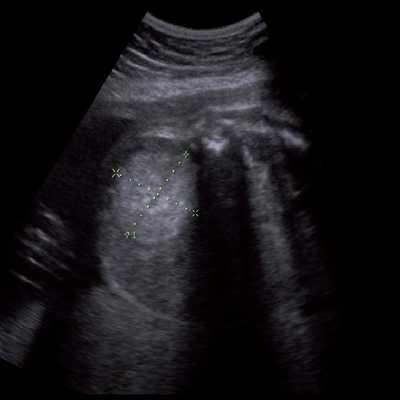

Под диафрагмой справа визуализировалось гиперэхогенное опухолевидное образование несколько неоднородной солидной структуры, с четкими ровными контурами, размером 50x38x35 мм. К нижнему полюсу данного образования прилежала правая почка, имеющая нормальные размеры, форму и структуру. Нижняя полая вена была смещена кпереди и влево. Обращала на себя внимание выраженная гепатомегалия, причем структура печени не была однородной. Она содержала множественные гиперэхогенные включения размерами до 17 мм, окруженные тонким гипоэхогенным периферическим ободком. Цветовое допплеровское картирование(ЦДК) демонстрировало интенсивную периферическую васкуляризацию опухоли (рис. 1-3).

Рис. 1. Нейробластома правого надпочечника плода. Беременность 31 нед 4 дня.

Рис. 2. Кровоток в нейробластоме плода. Цветовое допплеровское картирование. Отчетливо виден питающий сосуд, огибающий образование по его периферии. К нижнему полюсу образования прилежит интактная почка плода.